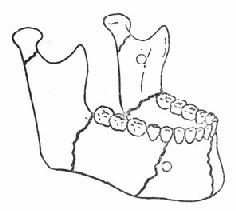

下颌骨是面部下1/3最大的骨胳,同时也是面部唯一能活动的骨胳。呈弓形,由下颌体、下颌角、下颌升支、喙状突和髁状突组成。骨皮质较厚,骨疏质较少,骨质结构比上颌骨坚实。但也有几处薄弱区域,如颏部正中联合、双侧颏孔区、双侧下颌角和双侧髁状突颈部,受到外力撞击时,均易发生骨折(图88-12)。此外,下颌骨是升颌肌群(即闭口肌群)和降颌肌群(即开口肌群)附着的地方,当下颌骨发生骨折时,由于肌肉相互间的平衡被破坏,骨折片常因咀嚼肌不同方向的牵引而产生不同方向的移位,致使开口、闭口活动受限,牙列变形,咬合错乱,咀嚼功能和语言功能出现障碍。

图88-12 下颌骨易发生骨折的薄弱区域